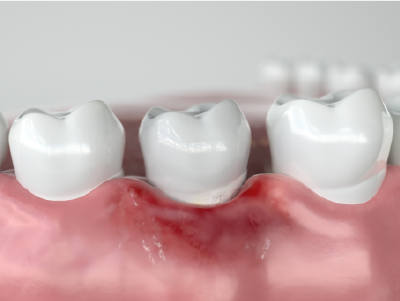

歯周病とは、歯周病菌によって歯茎の腫れ・出血を引き起こし、徐々に内部へ進行していき、最終的には歯を支える歯槽骨を溶かしてしまう病気です。

歯茎にのみ炎症が起きている状態。痛みがほとんどないため自覚しづらいですが、歯磨き時や硬い物を噛んだ時に出血することがあります。